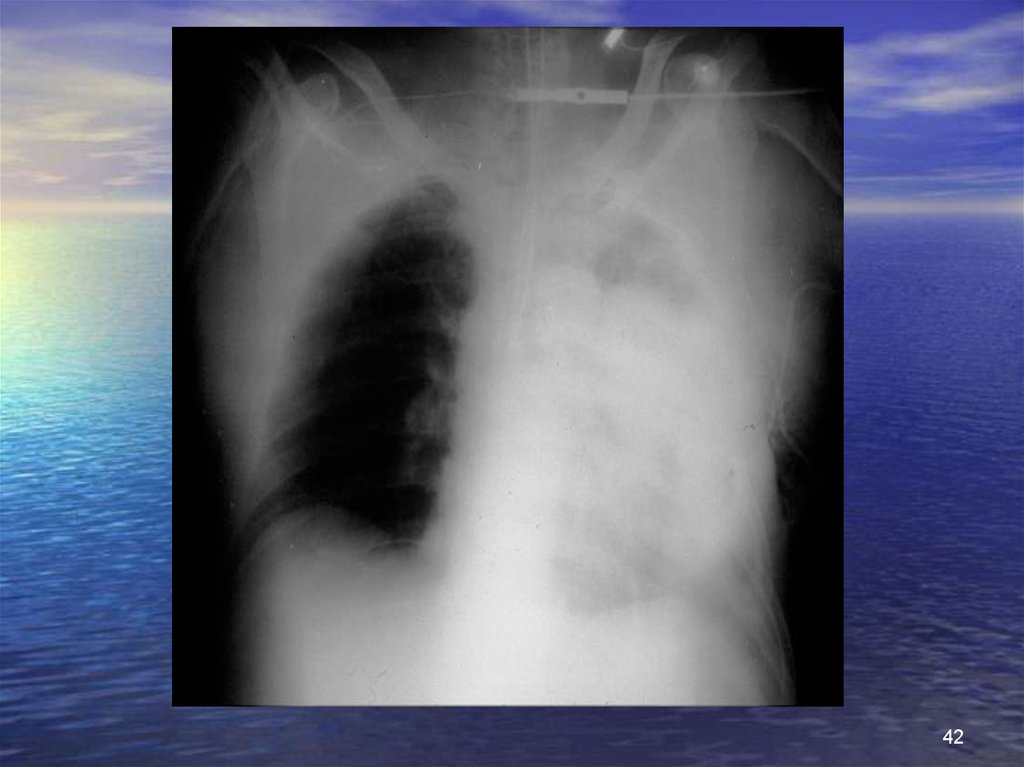

42.

42